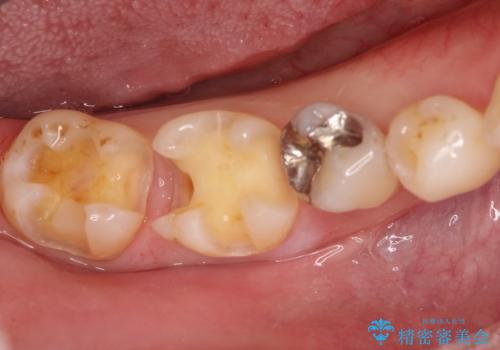

保険診療のCRインレーをセラミックインレーでやり直し

- 定期検診にて他院で治療された保険適用CRインレー部分(大臼歯2本)にむし歯を認めたため、セラミックインレーにて修復を行いました。

e-max プレスインレーにて修復治療を行っているため適合性及び審美性の高い治療を行うことができます